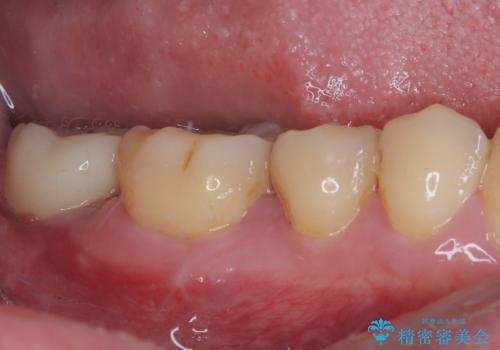

部分矯正を行ったこと治療期間は長くなりましたが、違和感のない咬み合わせを達成することができました。